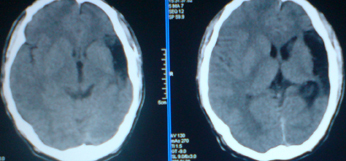

标题: CT24297:患者,男,左手抽搐致摔倒,平时无不适。 [打印本页]

标题: CT24297:患者,男,左手抽搐致摔倒,平时无不适。

外侧裂池蛛网膜囊肿或神经上皮囊肿,左侧颞顶叶脑萎缩。

1)左侧颞顶叶脑萎缩。2)左侧外侧裂池蛛网膜囊肿?

1.左侧顶叶脑软化并脑脑穿通畸形,左侧大脑半球萎缩。2.左侧外侧裂蛛网膜囊肿。

1、左侧颞顶叶脑软化灶。2、左侧大脑半球萎缩。没有其他病史吗?

萎缩改变,原因待查,病史?不会是囊肿。